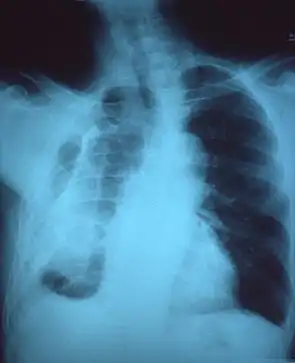

Фиброторакс, как правило, может быть диагностирован путем сбора истории болезни в сочетании с использованием соответствующих методов визуализации, таких как рентгенография грудной клетки или компьютерная томография (КТ). Эти методы визуализации могут обнаружить фиброторакс и утолщение плевры, которые окружают легкие. Присутствие утолщенной кожуры с кальцификацией или без нее являются общими признаками фиброторакса при визуализации. КТ помогает лучше чем рентген различать причину утолщение плевры: из-за избыточного отложения жира или истинного утолщения плевры.

Если фиброторакс тяжелый, утолщение может ограничить легкое на пораженной стороне, вызывая потерю объема легкого. Кроме того, средостение может быть физически смещено в сторону пораженной стороны. Уменьшение размера одной стороны грудной клетки (гемиторакса) при рентгенографии или компьютерной томографии грудной клетки предполагает хроническое рубцевание. Признаки основного заболевания, вызывающего фиброторакс, также иногда видны на рентгенограмме. КТ может показать признаки, подобные тем, которые видны на обычном рентгеновском снимке. Тестирование функции легких обычно демонстрирует результаты, согласующиеся с болезнью сжатия легких.